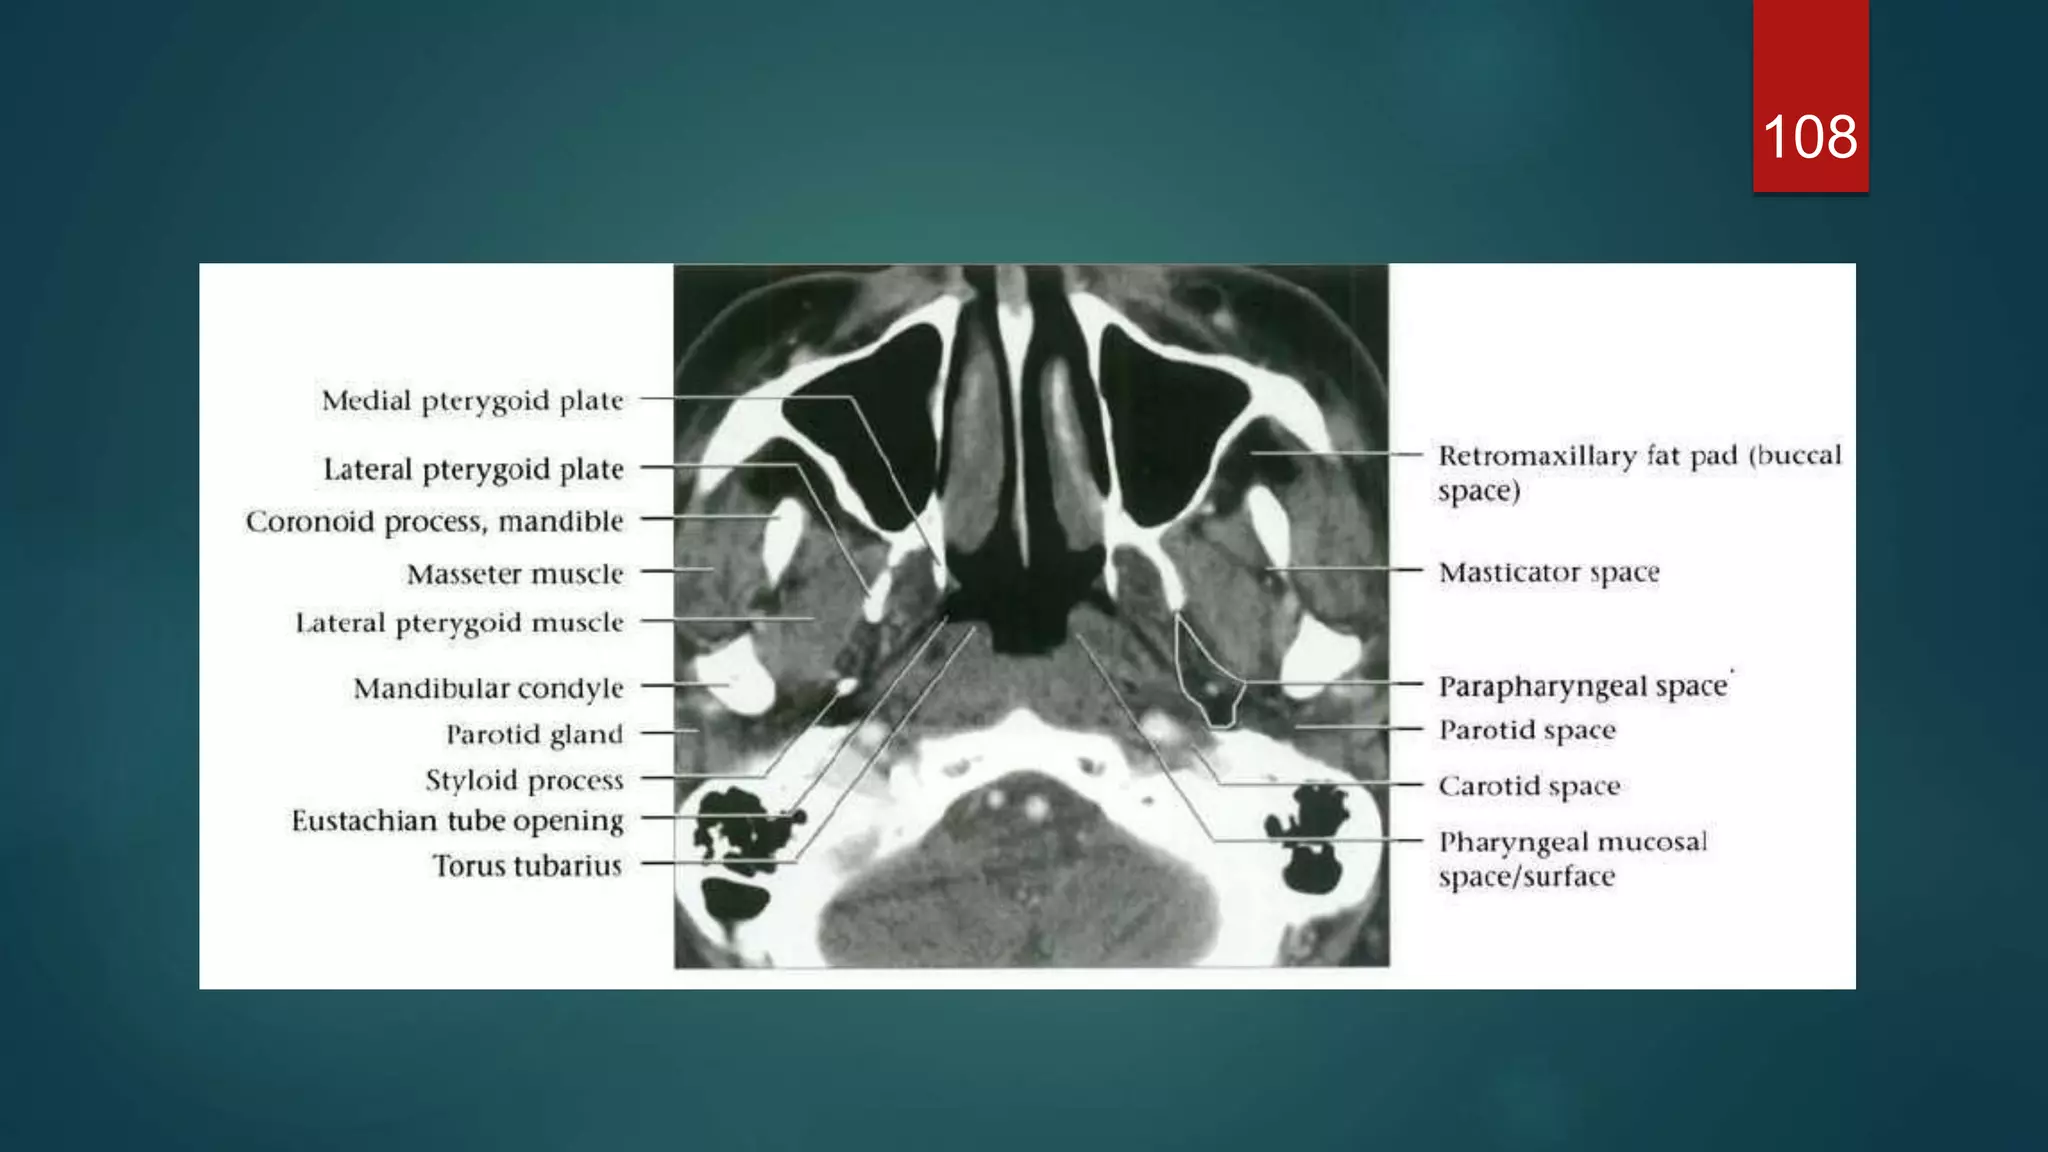

106

CT

108